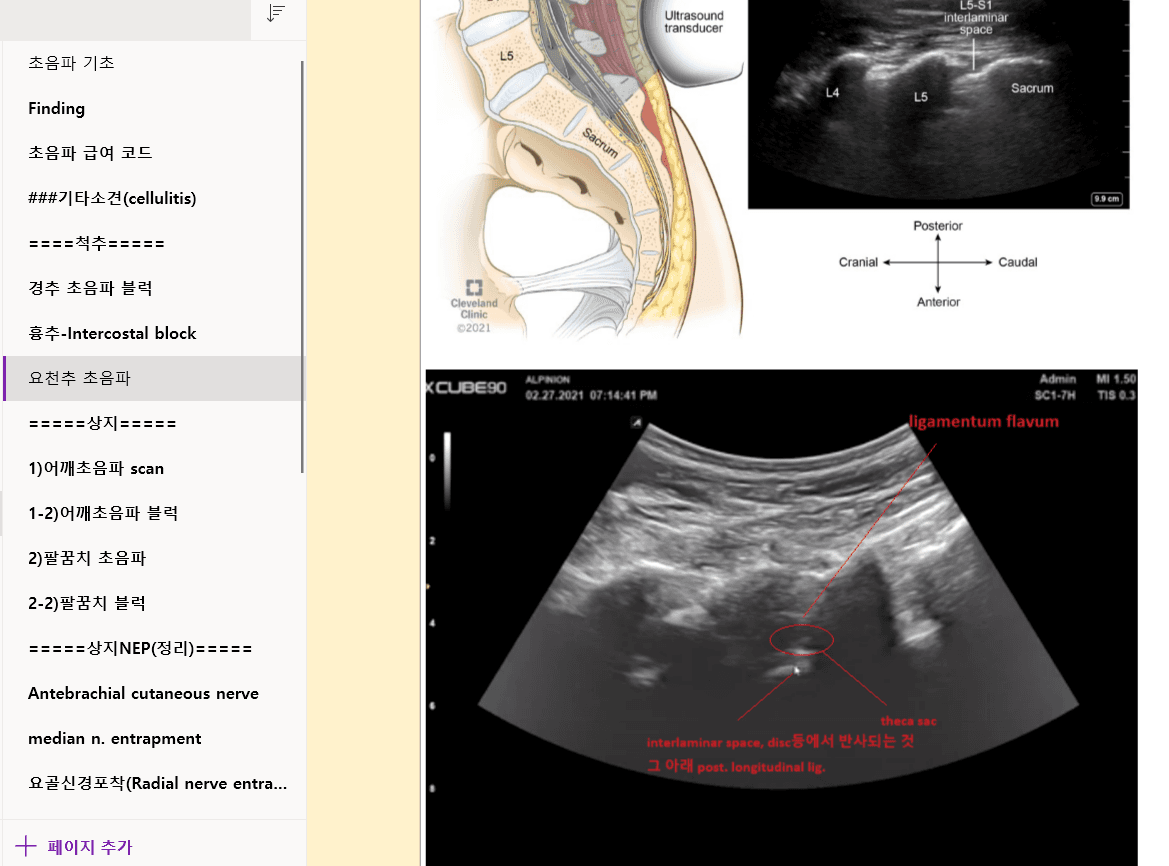

닥터노트 예시 화면

실제 닥터노트에서 제공하는 학습 자료와 세트오더를 확인하세요

피부과, 통증의학, IVNT, 세트오더 등 다양한 진료 분야의 실전 자료를 제공합니다